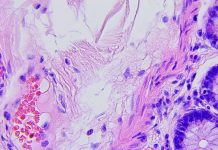

While asbestos imports, supply and use was banned from 1999, it is present in most buildings built before the year 2000. So, with many NHS hospital buildings containing asbestos, national asbestos-related cancer charity, Mesothelioma UK funded a study that aimed to explore the experiences of healthcare workers in the UK with mesothelioma and to develop recommendations for increasing awareness of the risk to healthcare workers.

The ‘MAGS’ study was carried out by researchers at the University of Sheffield. Mags Portman was a 44-year-old award-winning NHS doctor, wife and mother of two young sons. She was diagnosed with mesothelioma from asbestos exposure and died in 2019.

Mesothelioma: Preventable, but no cure

The Government and the public mistakenly seem to think that asbestos is a problem that’s been solved. Despite the UK finally banning asbestos in 1999, it is still very much present in many of our buildings and so the risk of exposure to asbestos is still with us every day. It only takes the inhalation of very low levels of asbestos fibres to be struck down years later with mesothelioma, a cruel cancer that is not survivable.

We do not have a cure for mesothelioma, but it’s a preventable cancer for future generations with the removal of asbestos from all our buildings. The Government’s blunt rejection of the recommendation from the Work and Pensions Select Committee for a dedicated programme for the phased removal of asbestos is numbing.